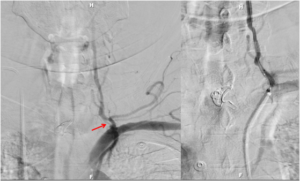

Stent Retriever with Flow Restoration

A stent is a tubular piece of mesh that can be placed inside of a blood vessel to maintain the blood vessel’s patency. In the setting of acute ischemic stroke, stent placement enables entrapment of the thrombus between the stent and the vessel wall to provide fast recanalization and to restore antegrade blood flow.

Flow restoration may rapidly re-establish oxygen supply in the brain region that has been deprived of the oxygen and nutrients that the blood supplies and removes the metabolic biproducts that are produced. Flow restoration also enhances the efficacy of thrombolytic drugs (ie. clot busters).

“Stent retrievers”, as they have been named, are a technology that haverevolutionalized the treatment of acute ischemic stroke. Stent retrievers allow thrombectomy to be performed by first deploying the stent inside of the clot and then pulling back the deployed stent into the guide catheter. In this scenario, the struts of the stent engage the thrombotic material and allow removal of the clot for the patient’s body.

Particularly advantageous is that the stent is applicable repeatedly and can be used even in small peripheral vessel branches (eg, M2 segments). In contrast with conventional stent systems, stent retrievers require no anticoagulation, as the stent is not deployed permanently.

Clot Extraction using Aspiration Systems (ADAPT technique)

The ADAPT technique is a new method for the treatment of acute ischmemic stroke that utilizes direct aspiration on the first pass with an extremely flexible and trackable large bore aspiration catheter as the primary method for vessel recanalization. Initial results with this technique have resulted in favorable patient outcomes.